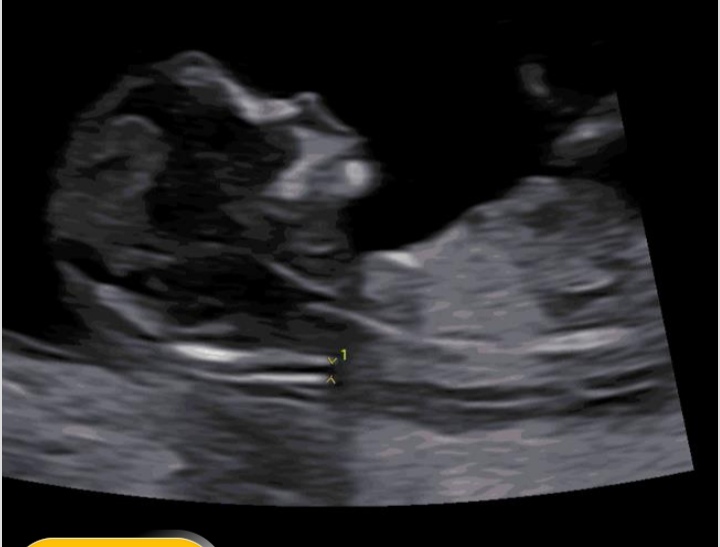

iambanoo مدیر عضویت: 1399/06/10 تعداد پست: 3993 عنوان بیاین نصف شب منو بِرَهانید از فکر زیاد عکس | مشاهده متن کامل بحث + 170 بازدید | 31 پست اگه بلدین بگین بچه من چیه🥲 سلنوفیل 🌙🌕 امروز | 01:48 0 نفر لایک کرده اند ... گزارش تاپیک نامناسب

زنخوشتیپ۲۲۲۲۲۲۲۲۲۲۲۲ عضویت: 1401/10/05 تعداد پست: 4173 اون که انگار کشیده شده رو به بیرون بند نافه؟ اره دختر قشنگمممم خیلی دوست میدارم...